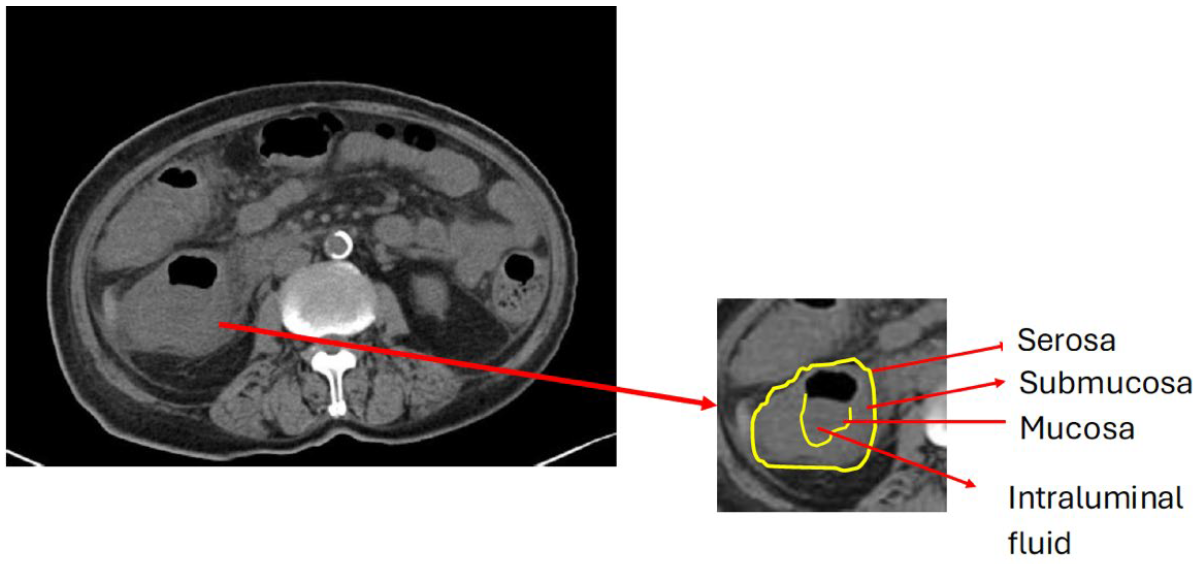

藉此,複習大腸腸壁分層的解剖構造。正常腸壁分層有: Mucosa, Submucosa, Muscularis propria, Serosa。某些疾病誘發大腸發炎的時候,CT上有機會看到這些分層,如下(橫切圖):

病灶的發炎的腸壁分層會被顯影劑顯現出來,我們稱之為target Sign,如下 :

(圖自https://litfl.com/abdominal-ct-enteritis-and-colitis/)

再回到這次討論的個案,雖然因腎功能不佳,而未注射靜脈顯影劑的影像條件,但仍隱約可見target sign,如圖二(橫切)

圖二腹部電腦斷層(未施打靜脈顯影劑) (橫切面)。 左圖,升結腸腸壁明顯腫脹,腸壁的腫脹。右圖,升結腸腸壁腫脹,腸壁腫脹由黃色箭頭指出,對比腹壁正上方的腸壁,紅色箭頭指出電腦斷層下的腸壁分層。